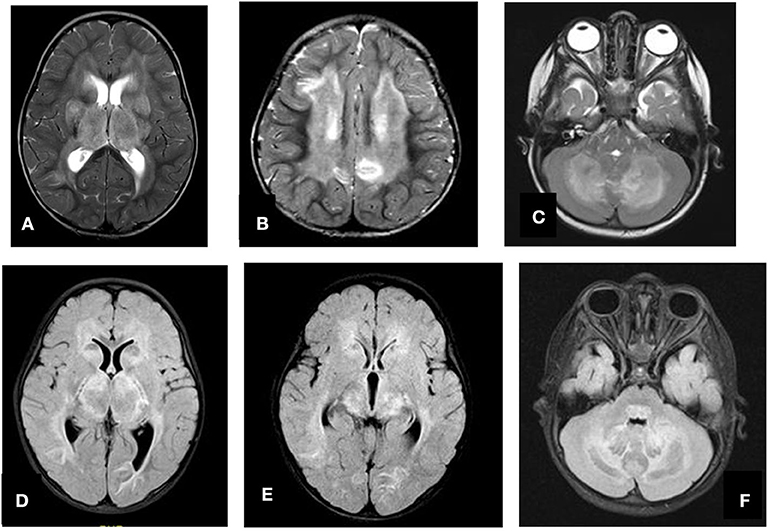

A total of 14 patients with ANEC were identified; two patients were excluded due to the inability to meet the ANEC radiological criteria. Patients' ages ranged from 10 months to 6 years (mean 30.92 months, median 22 months, standard deviation 20.63). Nine patients (75%) were female. All patients presented with preceding febrile illness in the form of upper respiratory tract infection (URTI) symptoms, or gastrointestinal symptoms in the form of vomiting or diarrhea, and altered level of consciousness. Seizures were the initial presentation in eight cases (66.7%). Brain imaging was carried out using Axial, Sagittal, and Coronal T1,T2, FLAIR, diffusion, and susceptibility weighted images which showed characteristic high signal intensity on axial T2 and FLAIR with variable degree of involvement of both thalami in all cases. Diffusion restriction was also seen, while the susceptibility sequence showed dark signal intensity with blooming, indicating hemorrhagic changes. Out of 12 patients, five (41.7%) had brainstem involvement. Follow up brain MRIs were done 2–3 months after the initial presentation, which showed signs of improvement on 33.3%, and 66.7% (n = 8) showed no signs of improvement. The clinical and radiological presentations are summarized in Tables 1, 2. Figures 1–4 show brain MRIs for selected patients.

Figure 4. Axial T2 (A–C) and FLAIR (D–F) showing swelling and abnormal high signal intensity of both thalami, basal ganglia, and cerebellum.